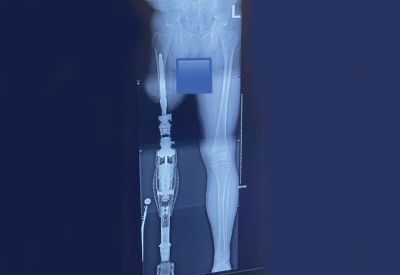

Like so many personal stories within our limb loss community, Djibril Kande’s path as a new amputee didn’t unfold in a straight line. It’s layered with moments of uncertainty, resilience, and quiet perseverance that those who have lived through limb loss uniquely understand.